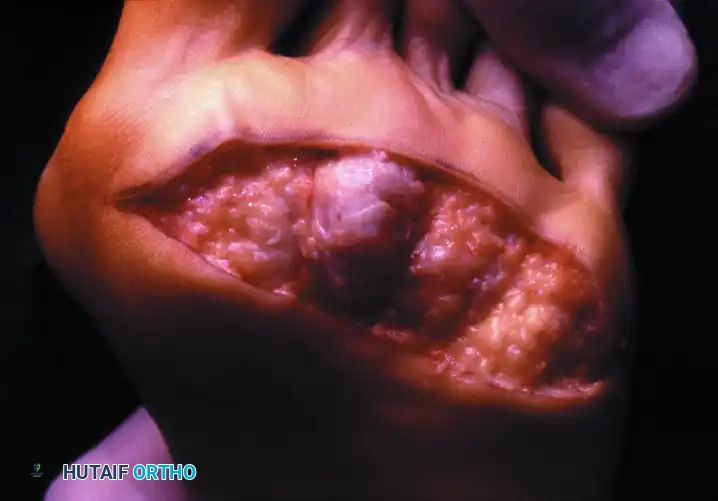

Preoperative Presentation: Multiple severe deformities, including hallux varus or valgus, dorsal dislocation of the lesser MTP joints, and intractable plantar ulcerations.

Postoperative Result: One year following arthrodesis of the first MTP joint and resection of the lesser metatarsal heads. The forefoot is plantigrade, the toes are realigned, and the plantar keratoses have resolved, allowing the patient to ambulate comfortably in accommodative footwear.